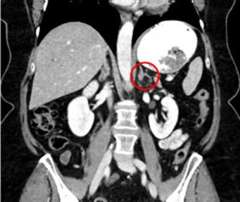

When patients have images taken of their abdomen with a CT scan or MRI, it is very common to see an adrenal nodule. In fact, we see adrenal nodules in 4 out of every 100 people that get a CT or MRI. An adrenal nodule is when normal tissue grows into a lump. Most incidental adrenal nodules do not cause health problems. However, they need to be evaluated for signs of excess hormone production or suspicion of malignancy. Because we often find adrenal nodules or masses when we were not looking for them, doctors will informally call these “incidentalomas.”

Adrenal tumor: Small incidentally discovered adrenal mass

An incidentally discovered adrenal mass is a growth on the adrenal gland that is discovered "by accident" on a scan (typically at CT scan or MRI of the abdomen) performed for another reason, such as abdominal pain. As the availability and speed of scanners in developed countries increased from the 1980s onward, people received more and more scans, leading to the growing discovery of adrenal masses. The prevalence of incidental adrenal masses has varied from 0.5% to 7% in different studies. We know that older people are more likely to have incidental adrenal masses. Most of them are unilateral (just on one side) and most are benign, nonfunctional tumors (adenomas) that do not require surgery. However, up to 30% of incidental adrenal masses may require surgery, depending on (a) whether the mass is overproducing a hormone, or (b) whether there is concern for a malignant/cancerous mass.

Adrenal masses can overproduce several types of hormones, such as cortisol (causing Cushing's syndrome), aldosterone (causing hyperaldosteronism), and catecholamines (pheochromocytoma). Blood and/or urine tests measuring levels of these hormones should usually be performed in patients with incidentally discovered adrenal masses. The most common type of hormone overproduction in these tumors is mild autonomous cortisol secretion (MACS, formerly known as subclinical Cushing's syndrome). Depending on the imaging characteristics, such as size and density (the quantity of x-rays absorbed by a structure on CT scan), your doctor may recommend either removal of the adrenal mass or continued monitoring. Larger masses, such as those >4 cm (1.6 in) and those with high density (>10 Hounsfield units) are more concerning, whereas smaller adrenal masses and those with low density (<10 Hounsfield units, compatible with fat tissue) are less concerning.